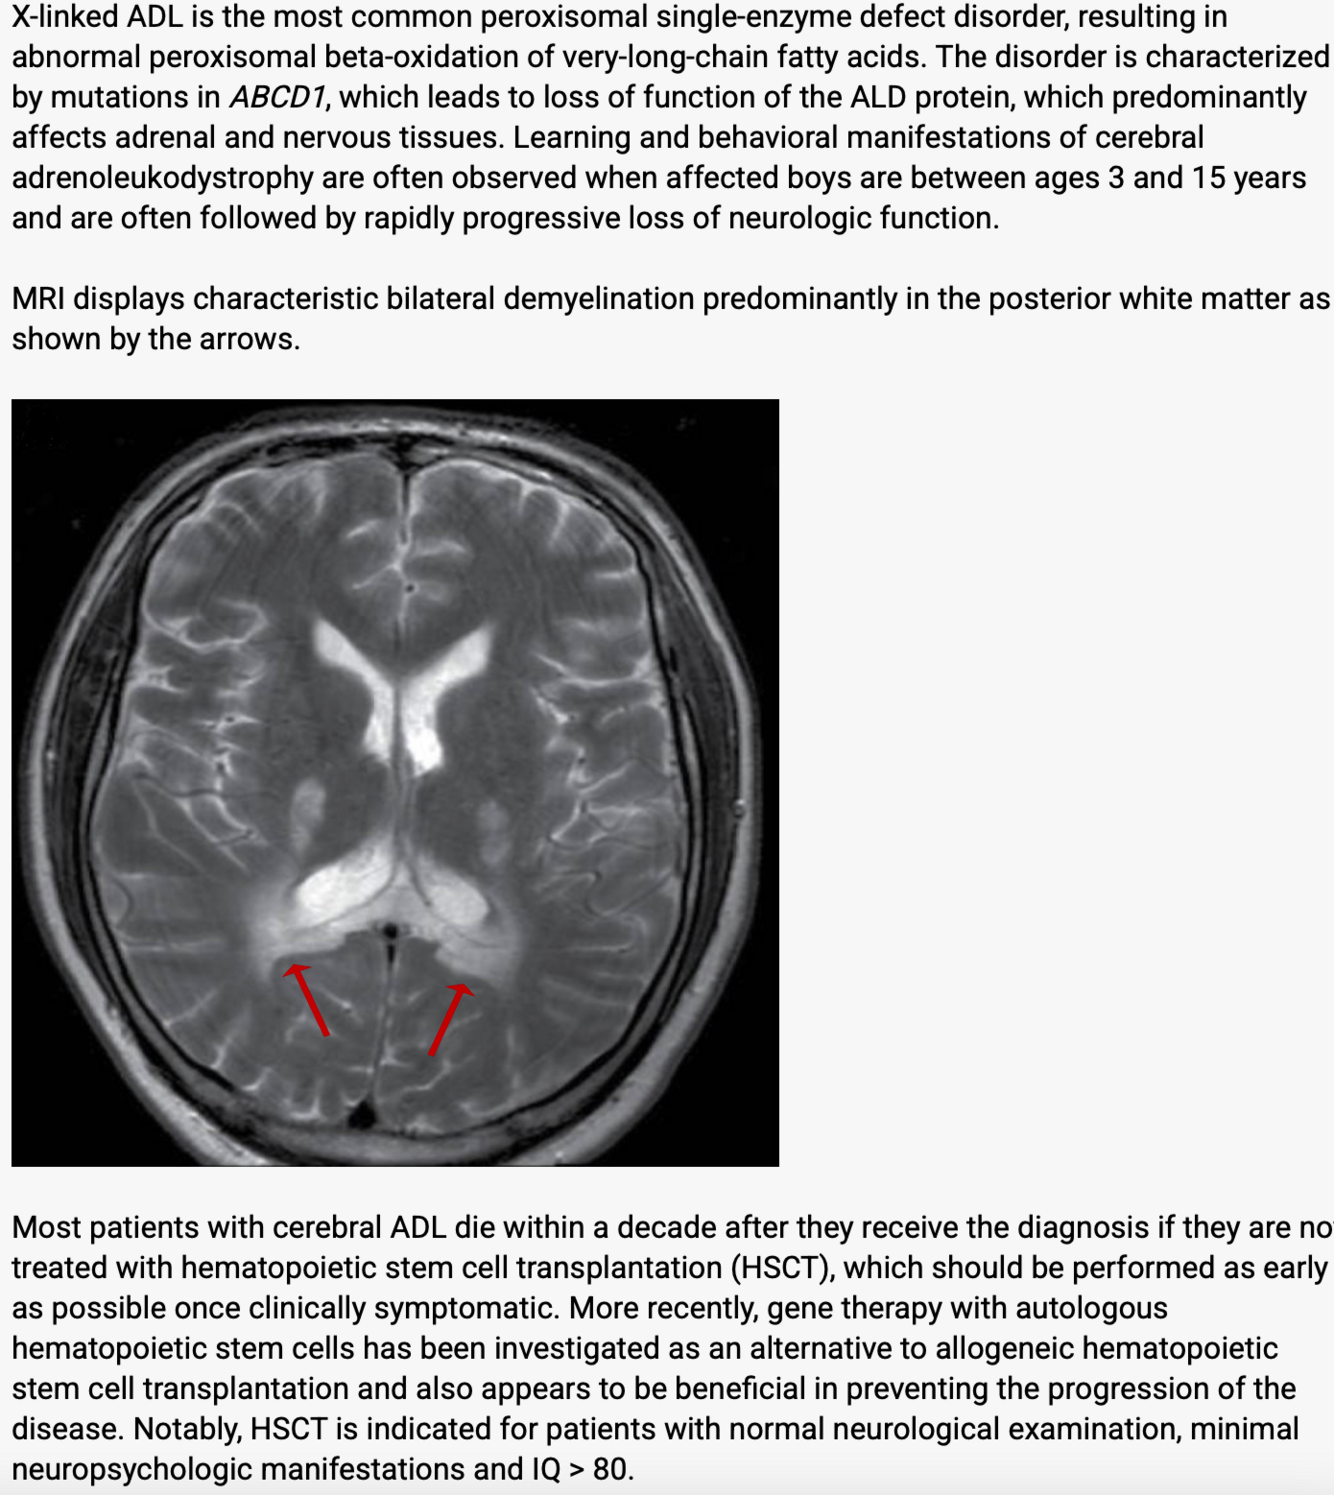

tx for X linked adrenal leukodystrophy?

If no significant neurological exam findings, psychiatric issues and IQ >80 good candidate

x-linked adrenoleukodystrophy typical initial sx? age? MRI findings?

behavioral changes, decline in schooling 2-10 occipital or selenium changes, symmetric